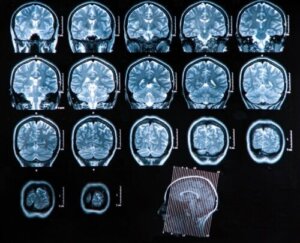

- Computertomografi: Dette har stor diagnostisk nytteværdi, da det giver mulighed for at kontrollere eventuelle forbindelser med den medicinske tilstand og etablere behandling i henhold til den tilsvarende fase. Denne teknik er også en god undersøgelse til at følge op på udviklingen af sygdommen efter gennemførelsen af behandlingen.

- Magnetisk resonansbilleddannelse: Dette er den bedste type billeddannelsesundersøgelse i forbindelse med diagnosticering af hjerneabscesser. Den er meget mere følsom end computertomografi og giver mange fordele ved påvisning af tidlig betændelse og ødemer og bedre differentiering mellem betændelsesområder og andre berørte strukturer.